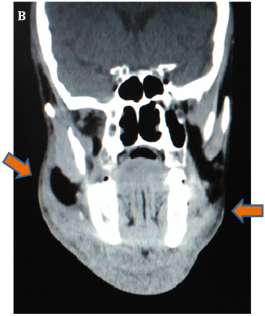

Ultrasound of the neck showed evidence of supraglottic edema, a finding that is confirmed by a computed tomography (CT) scan confirms supraglottitis and soft-tissue gas (Figure 1A & 1B). Leukocyte count was 36 x 103/mm3, and anion gap measurement indicates metabolic acidosis. After stabilization by administration of intravenous fluids and antibiotic agents, the patient was transferred to the operating room, where a drainage and cleaning of the anterior neck and floor of the mouth space was done through 3 incisions: two submandibular & one submental. Blood clots and necrotic tissues were optimally removed, tracheostomy was not indicated. The wounds were closed with drains (Figure 2A). Four days later, an additional drainage procedure was performed because of an infected fluid collection, and complete dental extraction was done. Patient was discharged in a good condition and at basal graft function (Figure 2B).

Figure 1: CT Skull, Neck & Upper Chest.